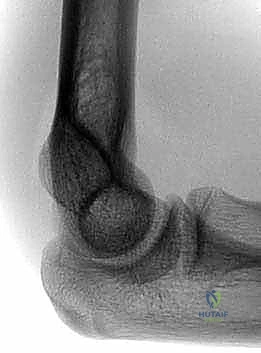

- الأشعة السينية (X-rays): هي الأداة الأساسية للتشخيص. يتم أخذ صورتين:

- صورة أمامية خلفية (AP View).

- صورة جانبية (Lateral View): وهي الأهم. في هذه الصورة، يقوم الطبيب برسم خط وهمي يمر عبر السطح الأمامي لعظم العضد (Anterior Humeral Line). في الوضع الطبيعي، يجب أن يمر هذا الخط عبر الثلث الأوسط من مركز التعظم لـ (Capitellum). إذا مر الخط أمامها، فهذا يؤكد وجود كسر متزحزح للخلف.

- يتم أيضاً قياس زاوية بومان (Baumann's Angle) لتقييم المحاذاة الجانبية وتجنب تشوه الكوع للداخل.